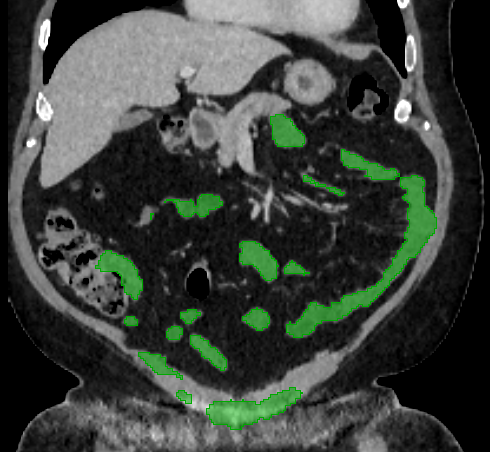

Over the years, there have been attempts to develop automatic methods for small bowel segmentation, especially using deep learning. The small bowel was included in segmenting multiple organs-at-risk for radiotherapy treatment planning of affected tissues, such as pancreatic and cervical cancers, in CT scans [8, 9, 13]. Although the results obtained for the small bowel are reasonable, some of their data included only the part of the small bowel that is closest to the target area, which needed to be dose-evaluated [8, 9]. In [13], the rough bowel location was detected instead of performing pixel-accurate small bowel segmentation. There have been only a few previous works dedicated solely to automatic small bowel segmentation [12, 14, 21]. While the specific anatomic relationship between the mesenteric vasculature and the small bowel is used to guide the small bowel segmentation in [21], a cylindrical shape constraint is applied during training of the small bowel segmenter in [14]. Although each of the works showed reasonable performance for particular datasets, their generalizability across different datasets was not evaluated. A CT scan is acquired using a specific imaging protocol depending on the purpose of the investigation, which includes the use of different contrast media and scan timing. Thus, the appearance of the small bowel may be different across datasets as exemplified in Figure 1. It is observed in our experiment that, when trained on one dataset, the model does not generalize well to another dataset due to the domain shift (section 3).

In this paper, we present a novel unsupervised domain adaptation method for small bowel segmentation, which is based on feature disentanglement. Although the absolute intensity values in CT scans (Hounsfield units) carry important information on specific substances of the human body, thus could provide a clue of being specific tissues and organs, they may be variable according to the imaging protocol. Figure 1 shows example CT scans that were acquired with and without oral contrast administration. The absolute intensity values are no longer a strong clue for the small bowel when we train and test across the datasets. Non-intensity features like texture and shape may be more useful. For example, local textures of the valvulae conniventes, which are circular folds on the inner surface of the small bowel, are more recurrent across the datasets.

3.2 Qualitative Evaluation

Figure 3 shows example segmentation results in 3D. The result corresponding to ‘feat. & out. level DA’ in Table 1 is compared to ours. We note that the only difference between them is whether the feature disentanglement is involved for the domain adaptation, thus could show its effectiveness. Fewer errors are observed for the proposed method. We believe this is because the proposed method explicitly concentrates on the features more transferable across the datasets, the non-intensity features in this work, by disentangling those features and applying adversarial learning directly to them during the adaptation process. Example reconstruction results from the auto-encoding architecture as well as segmentation results in coronal view can be found in supplementary material.